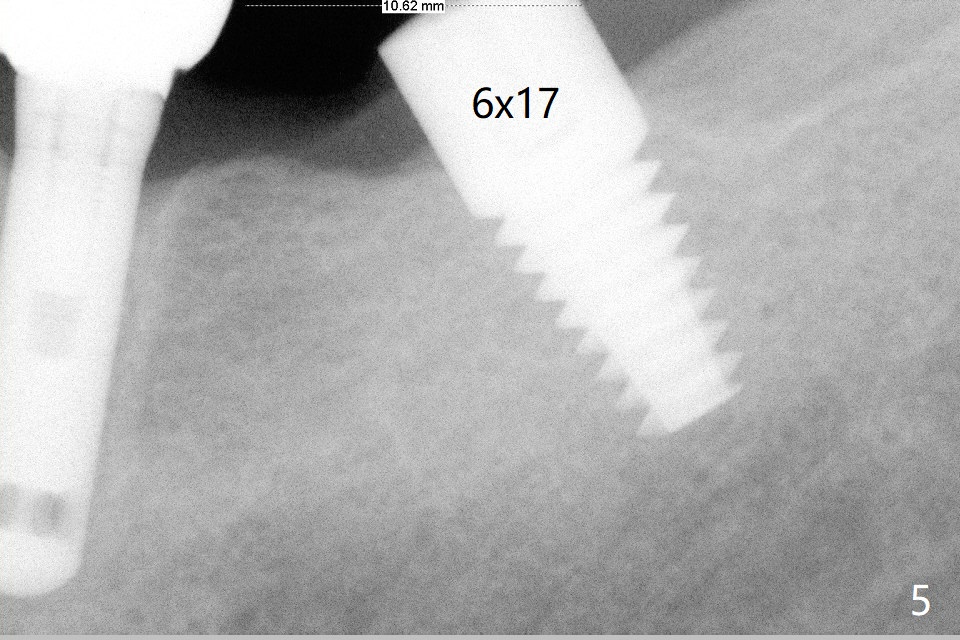

A 69-year-old man needs an implant at #18 (Fig.1,2 CT (sagittal and coronal sections)). In spite of use of surgical stent, the trajectory is not ideal (Fig.3-5). The following day the implant is removed with bone graft (Fig.6). In the 2nd placement, the trajectory is adjusted in each step (Fig.7-9 arrows) with long term stability (Fig.10,11).